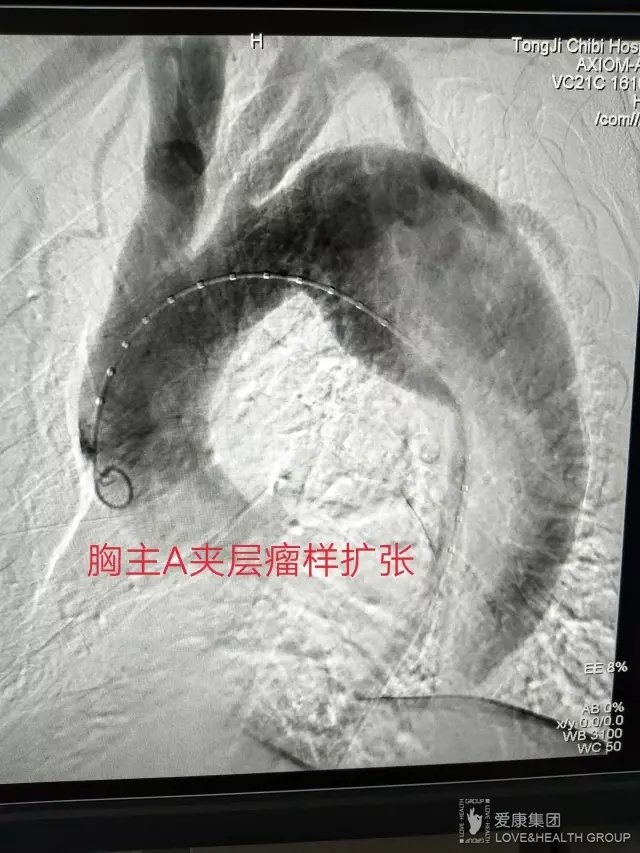

入院后第一時間行CTA血管成像顯示系胸主動脈夾層,胸腹主動脈內膜大范圍撕裂,病變自主動脈弓延續(xù)至髂血管,沿途內臟分支血管供血受累,假腔最大徑達6cm,隨時有破裂死亡風險。

同濟赤壁醫(yī)院介入科主任涂敬國高度重視此病例,第一時間反復耐心和病患充分溝通爭取信任配合,打消病患家屬思想疑慮;同時將病情上報爭取院級協(xié)調機制,以病人為中心精心準備介入圍手術期事宜。經(jīng)過多方準備,在上級教授的指導下,于2017年7月19日歷時近2小時及時為患者成功施行了胸主動脈夾層介入覆膜支架植入術。